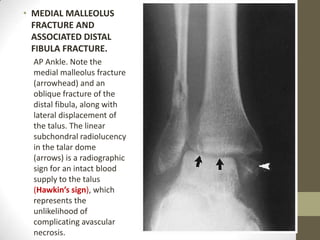

• MEDIAL MALLEOLUS

FRACTURE AND

ASSOCIATED DISTAL

FIBULA FRACTURE.

AP Ankle. Note the

medial malleolus fracture

(arrowhead) and an

oblique fracture of the

distal fibula, along with

lateral displacement of

the talus. The linear

subchondral radiolucency

in the talar dome

(arrows) is a radiographic

sign for an intact blood

supply to the talus

(Hawkin’s sign), which

represents the

unlikelihood of

complicating avascular

necrosis.